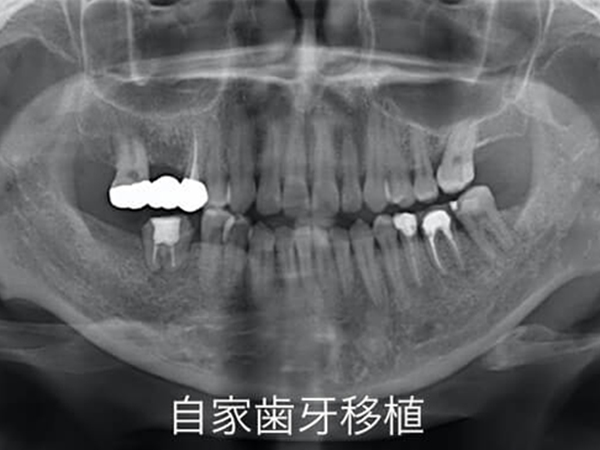

歯がない場所に、別の場所のご自身の歯を持ってきて、無い歯を補う治療です。

親知らずを用いて、歯のないところに移植することが多いです。

まず、歯がないところの骨を、移植される歯の形に合わせます。その後、歯を移植し、固定します。